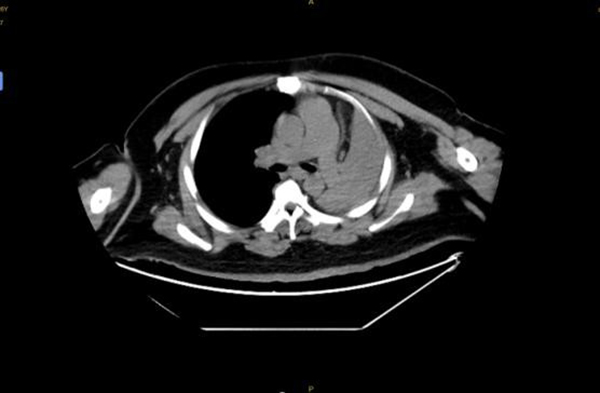

4月14日,王先生因“憋喘伴發(fā)熱咳嗽半月余”到徐州醫(yī)科大學附屬醫(yī)院急診就診。據(jù)王先生家人介紹,患者半個多月來,憋喘不斷加重,先后在徐州市多家醫(yī)院就診,考慮左肺不張伴感染,但通過積極抗感染治療,憋喘無改善并逐漸加重,同時出現(xiàn)發(fā)熱癥狀,體溫最高近39攝氏度。徐醫(yī)附院呼吸與危重癥醫(yī)學科何軍主任會診后,考慮患者智力異常,進食方式特殊,不排除誤吸的情況,閱片后發(fā)現(xiàn)左主支氣管內(nèi)存在異物可能,需行氣管鏡檢查進一步明確肺內(nèi)情況?紤]患者一般情況差,存在I型呼吸衰竭,肺部感染重等情況,于是將其收治在呼吸重癥監(jiān)護室(RICU)。

患者入院后進行高流量氧療和抗感染治療,因為其肥胖合并呼吸衰竭,肺部感染重,氣管鏡風險高,在與家屬充分溝通后,呼吸ICU團隊于4月15日為王先生行床旁氣管鏡檢查,鏡下發(fā)現(xiàn)左主支氣管內(nèi)一白色圓形異物,表面為壞死覆蓋,清除壞死組織后,異物質(zhì)硬,表面光滑,無法鉗取。同時患者病情危重、麻醉評估風險極高,在陳碧主任的主持下,呼吸ICU團隊經(jīng)過討論后決定行床旁氣管鏡取異物術。

季磊副主任醫(yī)師在楊翌、蔣宇及劉慧醫(yī)師的協(xié)助下,在全麻下經(jīng)氣管插管(8#)套管進鏡,左主支氣管內(nèi)可見被粘痰、壞死物包裹一圓形異物,清理后發(fā)現(xiàn)異物為花生粒,長徑約2cm,由于花生粒過大,無法通過8#氣管導管,于是將花生粒分解,通過使用圈套器、異物鉗以及網(wǎng)籃逐一將其取出,總共歷時1.5個小時。取出異物后,左主支氣管及其分支可見大量黃色膿性分泌物,予以充分吸除。

后續(xù)給與積極抗感染等治療,復查胸片示左肺不張改善,體溫正常,炎癥指標下降,再次復查氣管鏡下可見痰量較前明顯減少,總體病情好轉,4月23日轉到普通病房繼續(xù)治療;颊呒覍俦硎,輾轉三家醫(yī)院就醫(yī),還是徐醫(yī)附院最值得信任,對呼吸ICU全體醫(yī)護人員表達了敬意和衷心感謝。